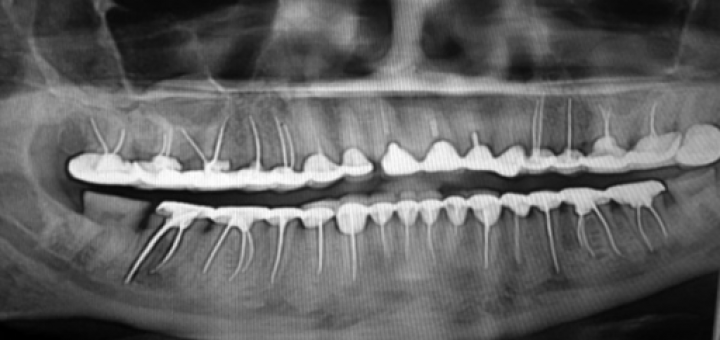

Root Canals May Cause Psoriasis

This is not the first post mentioning the root canal link to psoriasis on this blog. Leaving the dead piece of bone-like structure – tooth – in the body is one of the craziest and most killing procedures “modern” medicine does today! I am not going to rewrite here all the facts against the root canals (endodontic therapy). The point of this post is to give you directions to recommended books, videos and to make you start thinking about the......